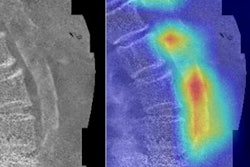

The tomosynthesis bone measurements strongly correlated with those from DEXA and micro-CT scans. Even with the small sample size, metrics such as bone mass, cortical thickness, and integral bone volume fraction all correlated with the reference measurements on a statistically significant basis.

Furthermore, the DWT metrics achieved sufficient repeatability, and the majority of structures hit the 0.7 threshold needed to demonstrate a strong positive correlation with reference metrics.

The DWT metric of bone volume fraction, in particular, looked like a useful correlate for bone mineral density. Bone volume fraction was not only significantly associated with patient age in the study but also was similar to volumetric measurements on CT and bone mineral density measurements on DEXA.